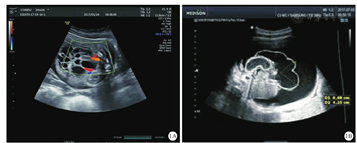

本例患儿为女性,G2P1,入院时年龄为31 min,因"生后腹胀31 min",以腹腔积液待查收入成都市妇女儿童中心医院新生儿科。母亲孕龄为24孕周时,胎儿超声检查提示胎儿腹腔囊性占位(图1A);40孕周时,产前胎儿超声检查提示胎儿腹腔囊性占位、腹腔大量积液、心包积液(图1B)。母亲孕期体健。无类似疾病家族史。患儿因"胎儿腹腔囊性占位、腹腔大量积液、心包积液",于胎龄40周时,在本院经剖宫产术娩出,生后1、5、10 min Apgar评分均为10分,出生体重为3 750 g。患儿生后腹胀明显。入院查体:体温为36.5 ℃、心率为140次/min、呼吸频率为43次/min,反应好,双肺未闻及啰音,心音有力、心律齐、心前区未闻及杂音,患儿腹胀明显,过脐腹围为45 cm,最大腹围为46 cm,腹软,无腹壁红肿及腹壁静脉曲张,触及腹部患儿无明显不适表现,肝、脾不能扪清,腹部听诊移动性浊音阳性,肠鸣音弱。